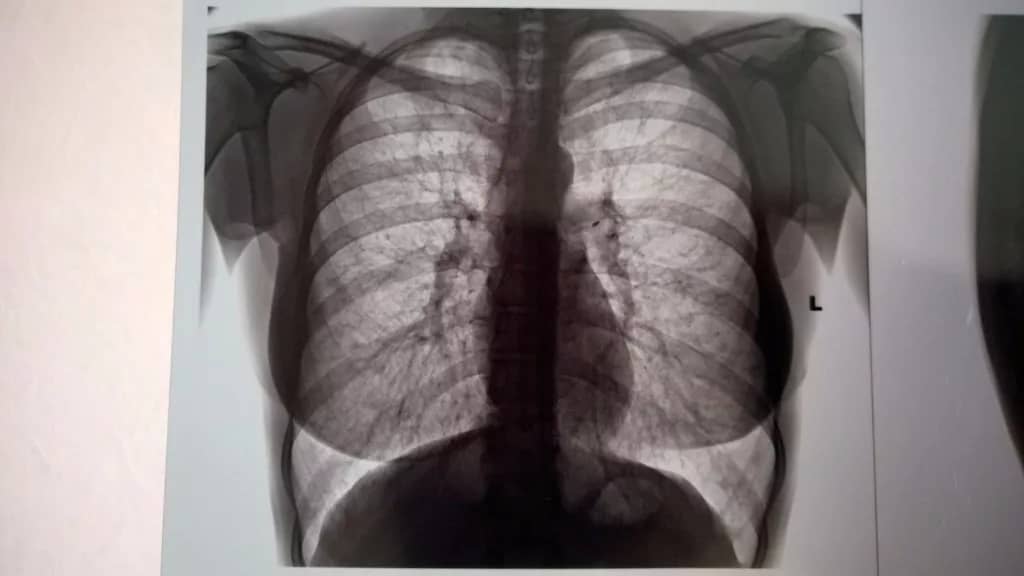

Флюорография — это важное и эффективное рентгенологическое исследование органов грудной клетки, которое позволяет своевременно выявлять заболевания легких, включая пневмонию, туберкулез, хронические воспалительные процессы и новообразования на ранних стадиях, когда симптомы еще отсутствуют.

В медицинской клинике «АКА» вы можете пройти флюорографию быстро, безопасно и с максимальным комфортом. Мы используем современное цифровое оборудование, которое обеспечивает минимальную лучевую нагрузку и высокое качество снимков, что позволяет нашим опытным врачам-рентгенологам точно и оперативно интерпретировать результаты обследования.

Флюорография — это рентгенологическое исследование органов грудной клетки, которое помогает выявить заболевания легких на ранних стадиях, такие как туберкулез, пневмония и другие патологии.